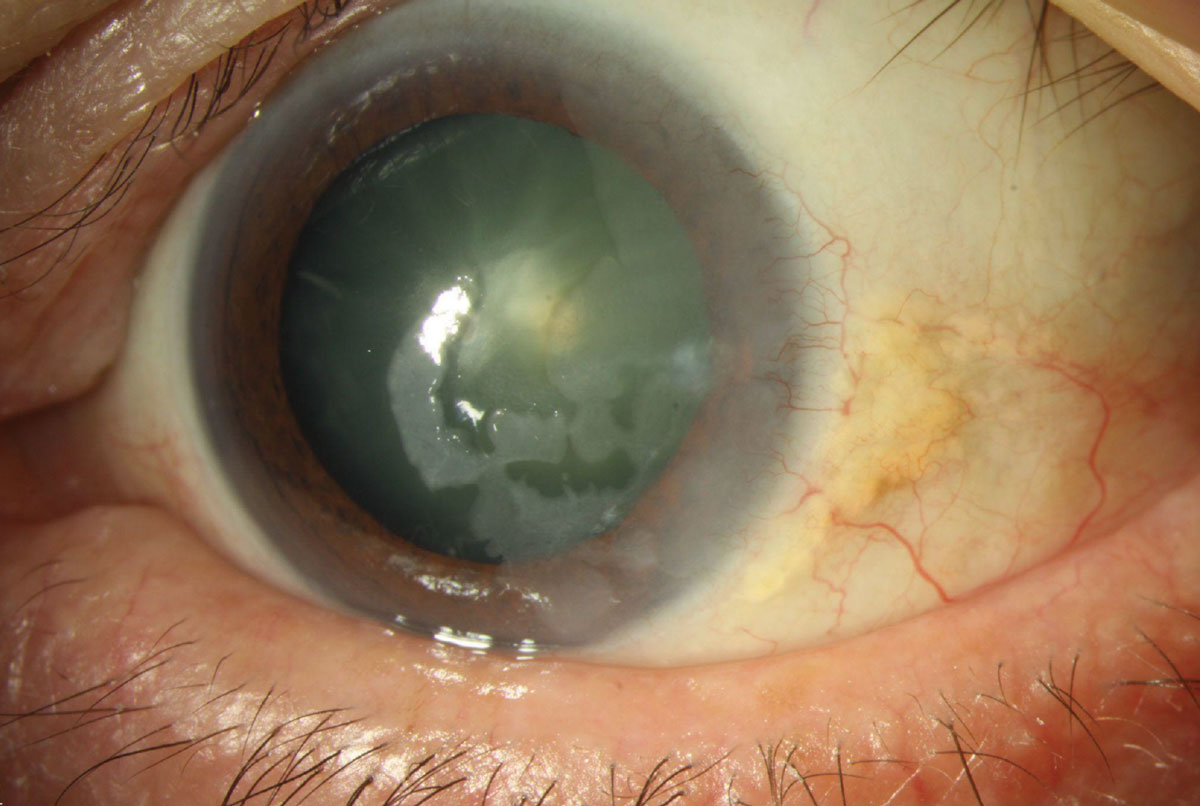

각막상피 이상성숙증(epithelial dysmaturation)은

주로 각막 상피만 침범하는 질환으로 광범위하게

얼어있는듯한 모양의 각막상피 혼탁이 발생하게됩니다.

각막상피의 투명도가 없어지면서 유백색의 병변으로 상피의 혼탁이 관찰되며,

주로 각막 상피만을 침범합니다.